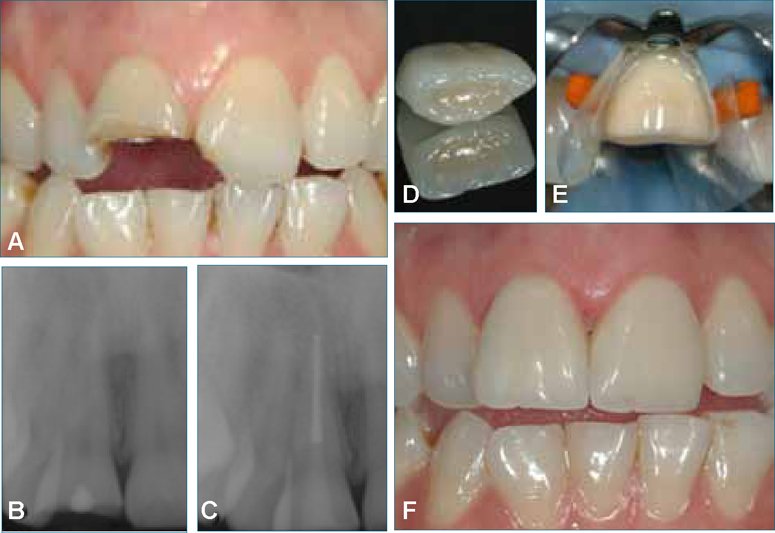

Tedavi edilen dişin genel durumu ve kaybedilen diş yapısı miktarı, dişin kalıcı bir kompozit dolgu veya diş kronu ile en iyi şekilde restore edilip edilmeyeceğini belirleyecektir. Ön dişlerde önemsiz diş yapısı kaybı olan küçük çürükler için diş hekiminiz kök kanal prosedüründen sonra diş renginde bir dolgu yerleştirebilir.

Diş hekiminiz kanal tedavisi görmüş bir dişin kanal yenilme tedavisiyle diş kronu yerleştirilmesini önerecektir. Kanal tedavisi görmüş dişler kırılgan olabilir ve bir diş kronu gelecekteki bakteriyel kontaminasyona ve kırılmaya karşı en iyi korumayı sağlar. Diş kuronu bir laboratuvarda yapılır ve dişinize özel olarak takılır. Kronlar porselen, metal veya ikisinin kombinasyonundan yapılır. Diş kronları ön veya arka dişlere yerleştirilebilir ve özellikle ağır çiğneme kuvvetlerine dayanması gereken azı dişleri için uygundur.